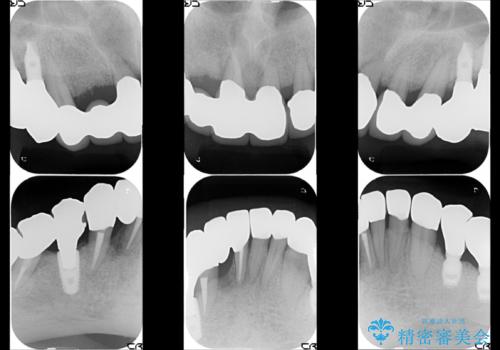

虫歯だらけ、歯周病 崩壊した口腔の再建 フルマウスリコンストラクション

- 歯周外科・インプラント・顕微鏡下根管治療などを含んだ総合的な治療を計画した。

かみ合わせの力が非常に強く、夜間の歯ぎしり・食いしばりもひどかったため、奥歯はメタルオクルーザルの設計でかぶせ物を製作しています。

インプラントの種類:Bicon / Zimmer spline

かぶせ物の種類:PFZ / PFM metal occlusal